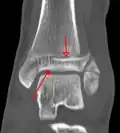

A triplane fracture of the ankle as seen on CT

CT

CT scans may be indicated when there is concern for a highly comminuted fracture or a fracture involving the joint surface.[10] This imaging may be used for surgical planning.